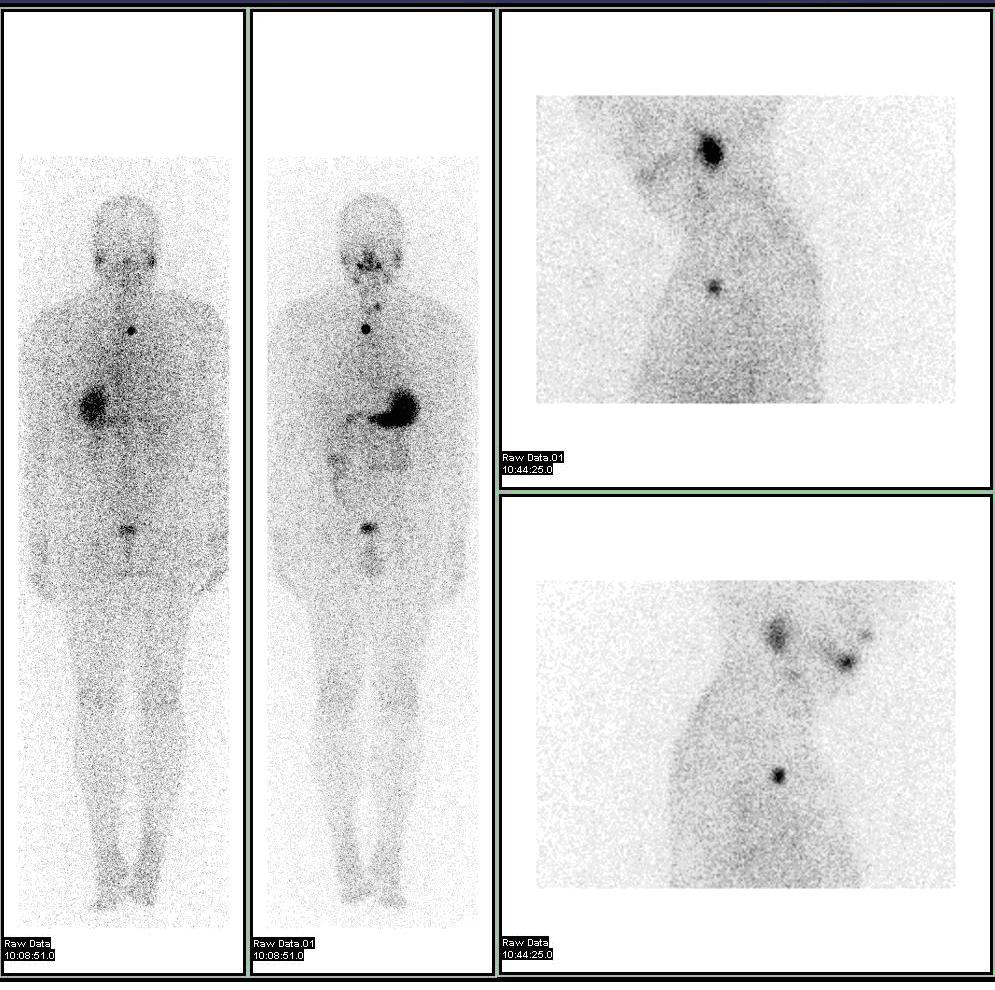

신티그래피(''신트'')는 내부 방사성핵종을 사용하여 2차원 영상을 만드는 것이다.[4]''SPECT''는 여러 투영의 감마 카메라 데이터를 사용하는 3D 단층 촬영 기법으로, 다른 평면에서 재구성할 수 있다. ''양전자 방출 단층 촬영''(PET)은 일치 검출을 사용하여 기능적 과정을 영상화한다.

핵의학 검사는 대부분의 다른 영상 기법과 달리, CT나 MRI와 같은 기존의 해부학적 영상과는 달리 조사 중인 시스템의 생리적 기능을 주로 보여준다. 핵의학 영상 연구는 일반적으로 특정 신체 부위(예: 흉부 X선, 복부/골반 CT 스캔, 두부 CT 스캔 등)에 초점을 맞춘 기존 방사선 영상보다 장기, 조직 또는 질병 특이적(예: 폐 스캔, 심장 스캔, 골 스캔, 뇌 스캔, 종양, 감염, 파킨슨병 등)이다. 또한 특정 세포 수용체나 기능을 기반으로 전신 영상을 얻을 수 있는 핵의학 연구가 있다. 예를 들어 전신 PET 스캔 또는 PET/CT 스캔, 갈륨 스캔, 인듐 백혈구 스캔, MIBG 및 옥트레오티드 스캔이 있다.

핵의학의 진단 검사는 질병이나 병리가 존재할 때 신체가 물질을 다르게 처리하는 방식을 이용한다. 신체에 도입된 방사성핵종은 종종 신체 내에서 특징적으로 작용하는 복합체에 화학적으로 결합되어 있으며, 이는 일반적으로 추적자로 알려져 있다. 질병이 있을 경우 추적자는 신체 주변에 분포되거나 다르게 처리되는 경우가 많다. 예를 들어, 리간드 메틸렌-디포스포네이트(MDP)는 골에 의해 우선적으로 흡수될 수 있다. 테크네튬-99m을 MDP에 화학적으로 부착함으로써 방사능을 수송하고 수산화인회석을 통해 골에 부착하여 영상화할 수 있다. 골절과 같이 생리적 기능이 증가하면 추적자의 농도가 증가하는 경우가 많다. 이는 종종 방사능 축적의 국소적 증가 또는 생리적 시스템 전체의 방사능 축적의 전반적인 증가인 "핫 스폿"의 출현으로 이어집니다. 일부 질병 과정은 추적자의 배제를 초래하여 "콜드 스폿"의 출현으로 이어집니다. 많은 추적자 복합체가 많은 다른 장기, 샘 및 생리적 과정을 영상화하거나 치료하기 위해 개발되었다.

신티그래피는 체내에 투여된 방사성 핵종을 이용하여 2차원 영상을 생성하는 핵의학 검사 방법이다. 전신 골 스캔, 심근 관류 스캔, 부갑상선 스캔, 간담 스캔, 폐 환기 및 관류 스캔, 갑상선 스캔 등 다양한 종류의 검사에 활용된다.2. 1. 2. 3차원 영상: SPECT, PET